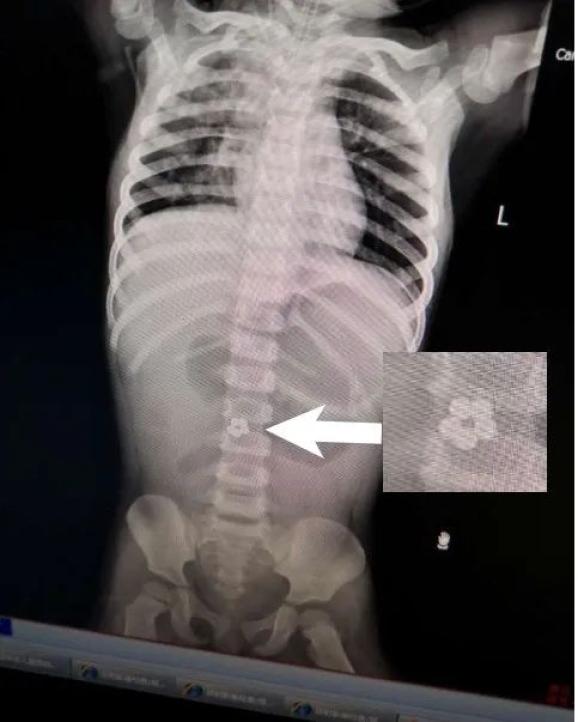

眼见治疗没效果,医生让孩子拍片检查。这一查——

在小静肚子里

居然发现

有5个连成圈的小球!

看完片子,妈妈后背一阵发凉:“这些小球……怎么像是之前买的玩具?”

2018年1月,深圳18个月大的小安(化名)不知道啥原因反复呕吐。就这样过了一周,孩子的精神逐渐变差。心急如焚的爸妈把孩子带到深圳市儿童医院,并做了个腹部X光检查,结果发现,小安的肠道内居然有5颗连在一起的圆珠子!